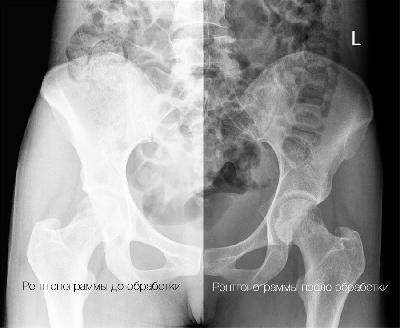

Заключенный Александр Китов в октябре 2013 года получил перелом шейки бедра. Из-за отсутствия адекватной медицинской помощи перелом неправильно сросся, что повлекло укорочение ноги на пять сантиметров, травматические изменения в тазобедренном суставе и искривление поясничного отдела позвоночника. В результате этого на протяжении трех лет человек испытывает постоянные физические боли и не может не только нормально передвигаться, но даже сидеть и элементарно помыть ноги.Как объясняют доктора, вопрос о вероятности излечения можно ставить после прохождения полноценного медицинского обследования. Вероятно, мужчине необходима операция с последующей реабилитацией. Но обследованием и лечением Китова заниматься не спешат.